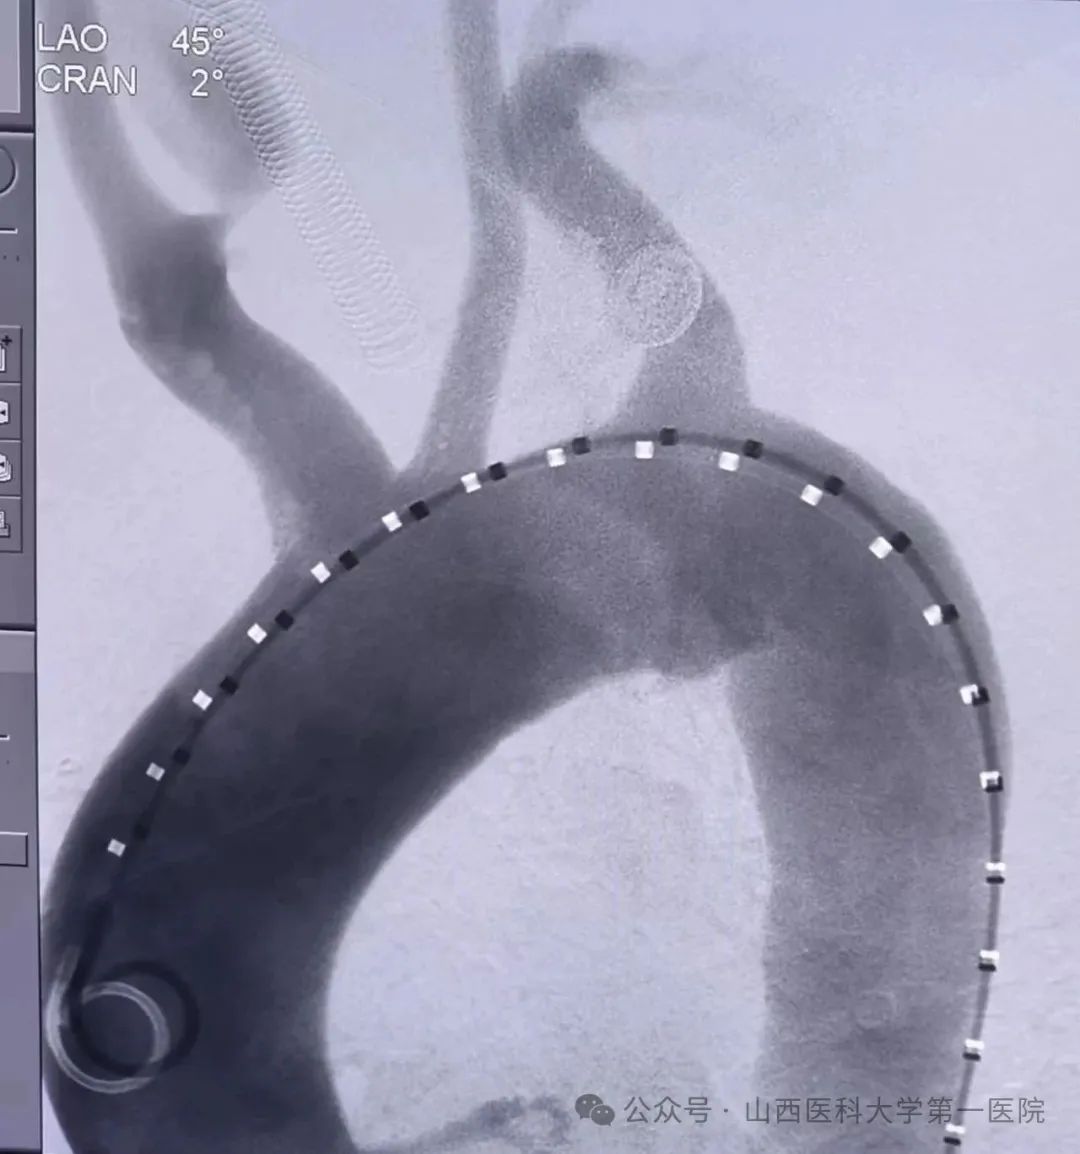

术中DSA影像 术后DSA影像

手术于当天上午8时30分开始,采取双股动脉和左肱动脉三路联合路径,将GORE分支型胸主动脉支架系统精准释放左颈总动脉开口端,完全覆盖病变部位,之后循预制导丝将覆膜支架经分支型胸主动脉支架分支重建左锁骨下动脉。左前斜位造影清晰显示主动脉弓上三大分支显影良好,穿透性溃疡消失,血流通畅,支架位置精准无内漏,手术成功。